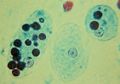

تحتوي الإنتاميبا المتحوصلة على أربع أنوية يتوسطها أجسام بروتينية تسمى الأجسام الكروماتيدية Chromatoids.

| مرحلة العدوى | Quadrinucleated cyst (لها أربع أنوية) | ||||||||||||||

| النواة | 'Ring and dot' appearance: peripheral chromatin and central karyosome | ||||||||||||||